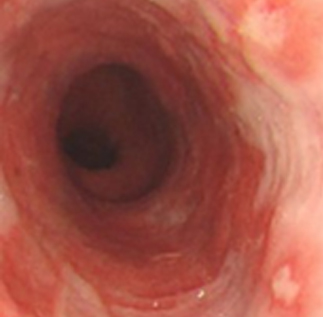

후비루 증상은 부비동 엑스레이나 비강 내시경을 통하여 비부비동염 여부를 확인해야 하며, 기침형 천식은 기관지 유발 시험, 호기 산화질소, 객담 호산구 검사 등으로 진단할 수 있습니다. 한편 위식도 역류 질환은 식도로 역류된 위속의 내용물로 인해 불편한 증상이나 합병증이 유발되는 상태를 말하며, 24시간 식도 산도 검사나 위내시경을 통하여 진단할 수 있습니다. 위산이 식도를 넘어 인두와 후두까지 역류하여 점막을 자극하는 경우 후두 내시경을 통하여 인후두 역류 질환을 진단할 수 있습니다.

상기도 기침 증후군 기침형 천식 위산 역류 질환

치료 전 기관지 유발 시험 검사 위식도 역류 질환

img img img

치료 후 기관지 유발 시험 검사 양성 인후두 역류 질환